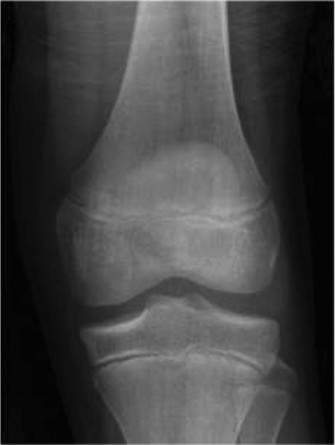

The risk of graft failure observed in pediatric patients with allograft reconstruction? CASE 17 A 10-year-old female soccer player presents to the sports clinic with a several month history of knee pain and swelling along the lateral joint line. The patient notes pain and a snapping sensation laterally. She also describes occasional mechanical symptoms as well. On physical exam she is unable to fully extend the knee. The patient otherwise has a stable ligamentous examination of the knee. Radiographs are obtained and shown in Figure 10–29.

Figure 10–29

The correct answer is (B). The patient’s clinical examination is concerning for meniscal injury (lateral joint line pain) with the snapping sensation concerning for an unstable meniscus. The radiographs demonstrate lateral joint space widening, cupping of the lateral tibial plateau, and a hypoplastic lateral tibial spine—all suggestive of a discoid meniscus. Discoid menisci are classified using the Watanabe classification as complete, incomplete, or Wrisberg (lack of posterior meniscotibial attachment to the tibia). Unstable variants create the classic “snapping” sensation. The diagnosis of a discoid meniscus can be made with three or more 5-mm sagittal images with meniscal continuity. As the patient has had several months of pain with

mechanical symptoms and swelling, reassurance is not appropriate. Although IT band tendonitis can cause “snapping” it is not accompanied by loss of extension and swelling. Corticosteroid injections should be utilized sparingly in the pediatric population; particularly when a diagnosis has not been made. The patient then obtains an MRI which is shown inFigure 10–30. The next appropriate step in management is: